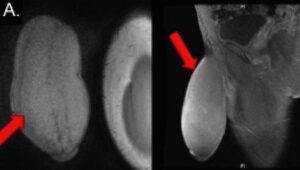

«Το μέγεθος του πέους είχε διογκωθεί σαν ένα μπαλόνι» τόνισε ο Rafael Carrion, ο ουρολόγους που εξέτασε τον νεαρό. Το πρόβλημα οφειλόταν σε ένα είδος αναιμίας, που ουσιαστικά μπλόκαρε τα αιμοφόρα αγγεία σε αυτό το σημείο του σώματος. Τελικά, η επέμβαση πήγε μια χαρά και ο 17χρονος δήλωσε πολύ ικανοποιημένος.

“Εάν θέλετε να δείτε την εικόνα κάντε κλικ. Προειδοποίηση για ακατάλληλο περιεχόμενο.“